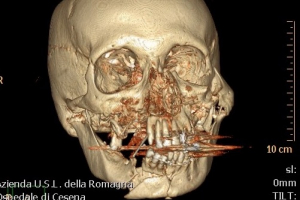

Traumatologia MXF